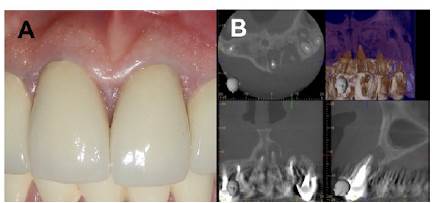

Paciente femenina de 67 años que acudió a la consulta por inflamación y supuración en la zona antero-superior, con sintomatología dolorosa, sin antecedentes médicos de importancia. El examen clínico revela coronas completas en los dientes 11, 12, 21, 22, 23, encía levemente marrón a nivel marginal de dichos órganos (Figura 1A). Se procedió a realizar una tomografía axial computarizada donde se evidenciaban zonas radiolúcidas y gran destrucción de las tablas óseas a nivel de los órganos dentarios implicados (Figura 1B).